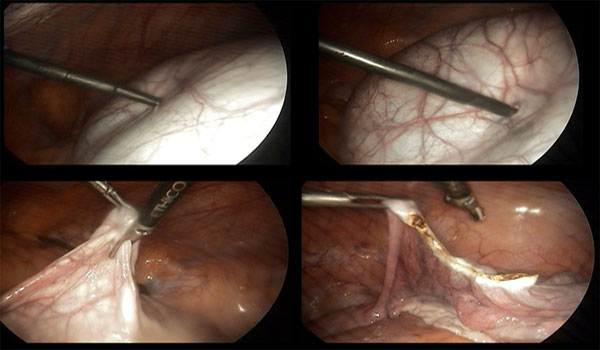

- மருந்துகள் மூலம் குணம் ஆகவில்லை என்றால் லேப்ராஸ்கோப்பி முறையில் அந்த நீர் கட்டிகளை உடைத்து விடவேண்டும்.

- அதற்கு கட்டியை மட்டும் எடுப்பதா-கர்ப்பபை முழுவதும் எடுப்பதா—ஓபன் அறுவைசிகிச்சையா-லேப்ராஸ்கோபியா என்பது நோயாளியின் வியாதியின் தன்மையை பொருத்து மாறும்